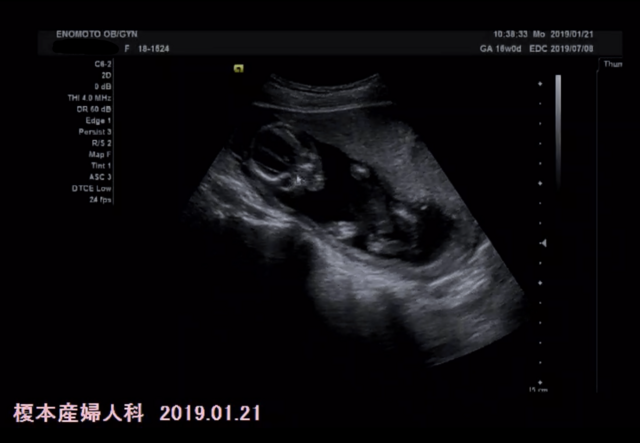

16週0日(16w0d・女の子)|yu0215ki さん(29歳)

エコー写真撮影時のエピソード:

パパも一緒にエコー見た!始めてのお腹からのエコー☆私よりパパの方が興奮してた(^O^)赤ちゃんは元気いっぱいで動き回ってた。手足を伸ばしたりして、背骨もしっかり出来てて順調で安心した( *ˊᵕˋ)

そして、今のところ女の子!でもまだへその緒で隠れてたりするからはっきり女の子とは言えないって^^でも元気で産まれてくれるならどっちでもいいや!